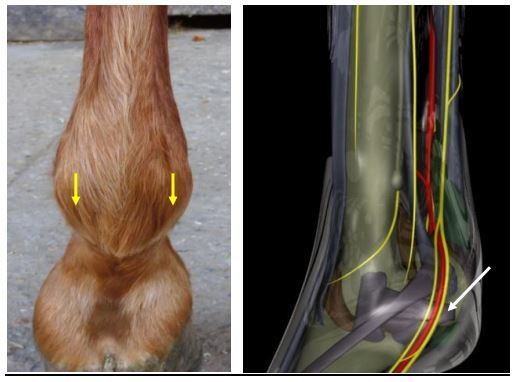

Where do you do a palmar digital nerve block (PDNB)?

Palpate the neurovascular bundle just proximal to the collateral cartilage of P3. The palmar digital nerve (PDN) lies most palmar. AIM DISTALLY